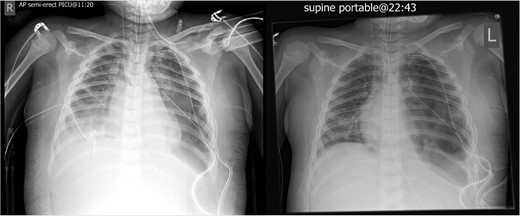

Post operatively, two left sided chest drains were left on free drainage. There were persisting smaller cavities within the left lung. Serial chest radiographs over the next 7 days demonstrated a persisting, increasing left pneumothorax and worsening consolidation of the left lung (Fig. 4). On the 8th post-operative day, the child suffered an acute respiratory deterioration with a reduction in oxygen saturations. The chest radiograph revealed a new right-sided tension pneumothorax which required emergency drainage (Fig. 5).

Worsening appearances of the left pneumothorax despite chest drains in situ.